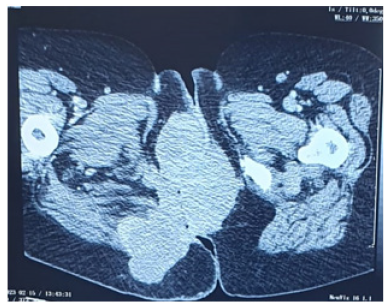

A 55-year-old woman presented with one year history of the presence of a painless mass on the anal region, on which diagnosis of GCT perianal is confirmed, patient has a surgical excision without radiotherapy or chemotherapy adjuvant. 4 years later, this patient arrived at a hospital with a painless mass on the anal region (Figure 1), the thoraco-abdominal and pelvic CT scan showing the presence of a right anal and para-anal mass measuring 130*81mm extended to the surrounding soft tissues and infiltrating the neighboring muscular structures on the right side and the perineal and buttock skin (Figure 2) with pulmonary metastasis.

Figure 2: CT scan showing the presence of a right anal and para-anal mass measuring 130*81mm extended to the surrounding soft tissues and infiltrating the neighbouring muscular structures on the right side and the perineal and buttock skin.